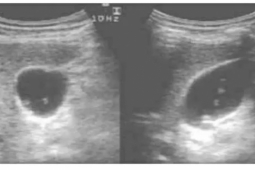

Vừa qua, các bác sĩ BVĐK Tâm Anh, TPHCM cho biết đã lọc máu cấp cứu kịp thời cho bệnh nhân nam T.T.V. (35 tuổi, quận 9) sau khi ăn nửa trái xoài.

Điều trị cho bệnh nhân, BSCKI. Tôn Minh Trí nhận định anh V. suy thận cấp trên nền suy thận mạn giai đoạn 5. Ngay lập tức, người bệnh được dùng thuốc hạ kali máu và chuyển đến khoa Hồi sức cấp cứu (ICU) để lọc máu liên tục. Sau 8 tiếng, người bệnh khỏe, ăn uống bình thường trở lại, được xuất viện và tiếp tục chạy thận định kỳ.

Anh V. được lọc máu tại bệnh viện. Ảnh: BVCC